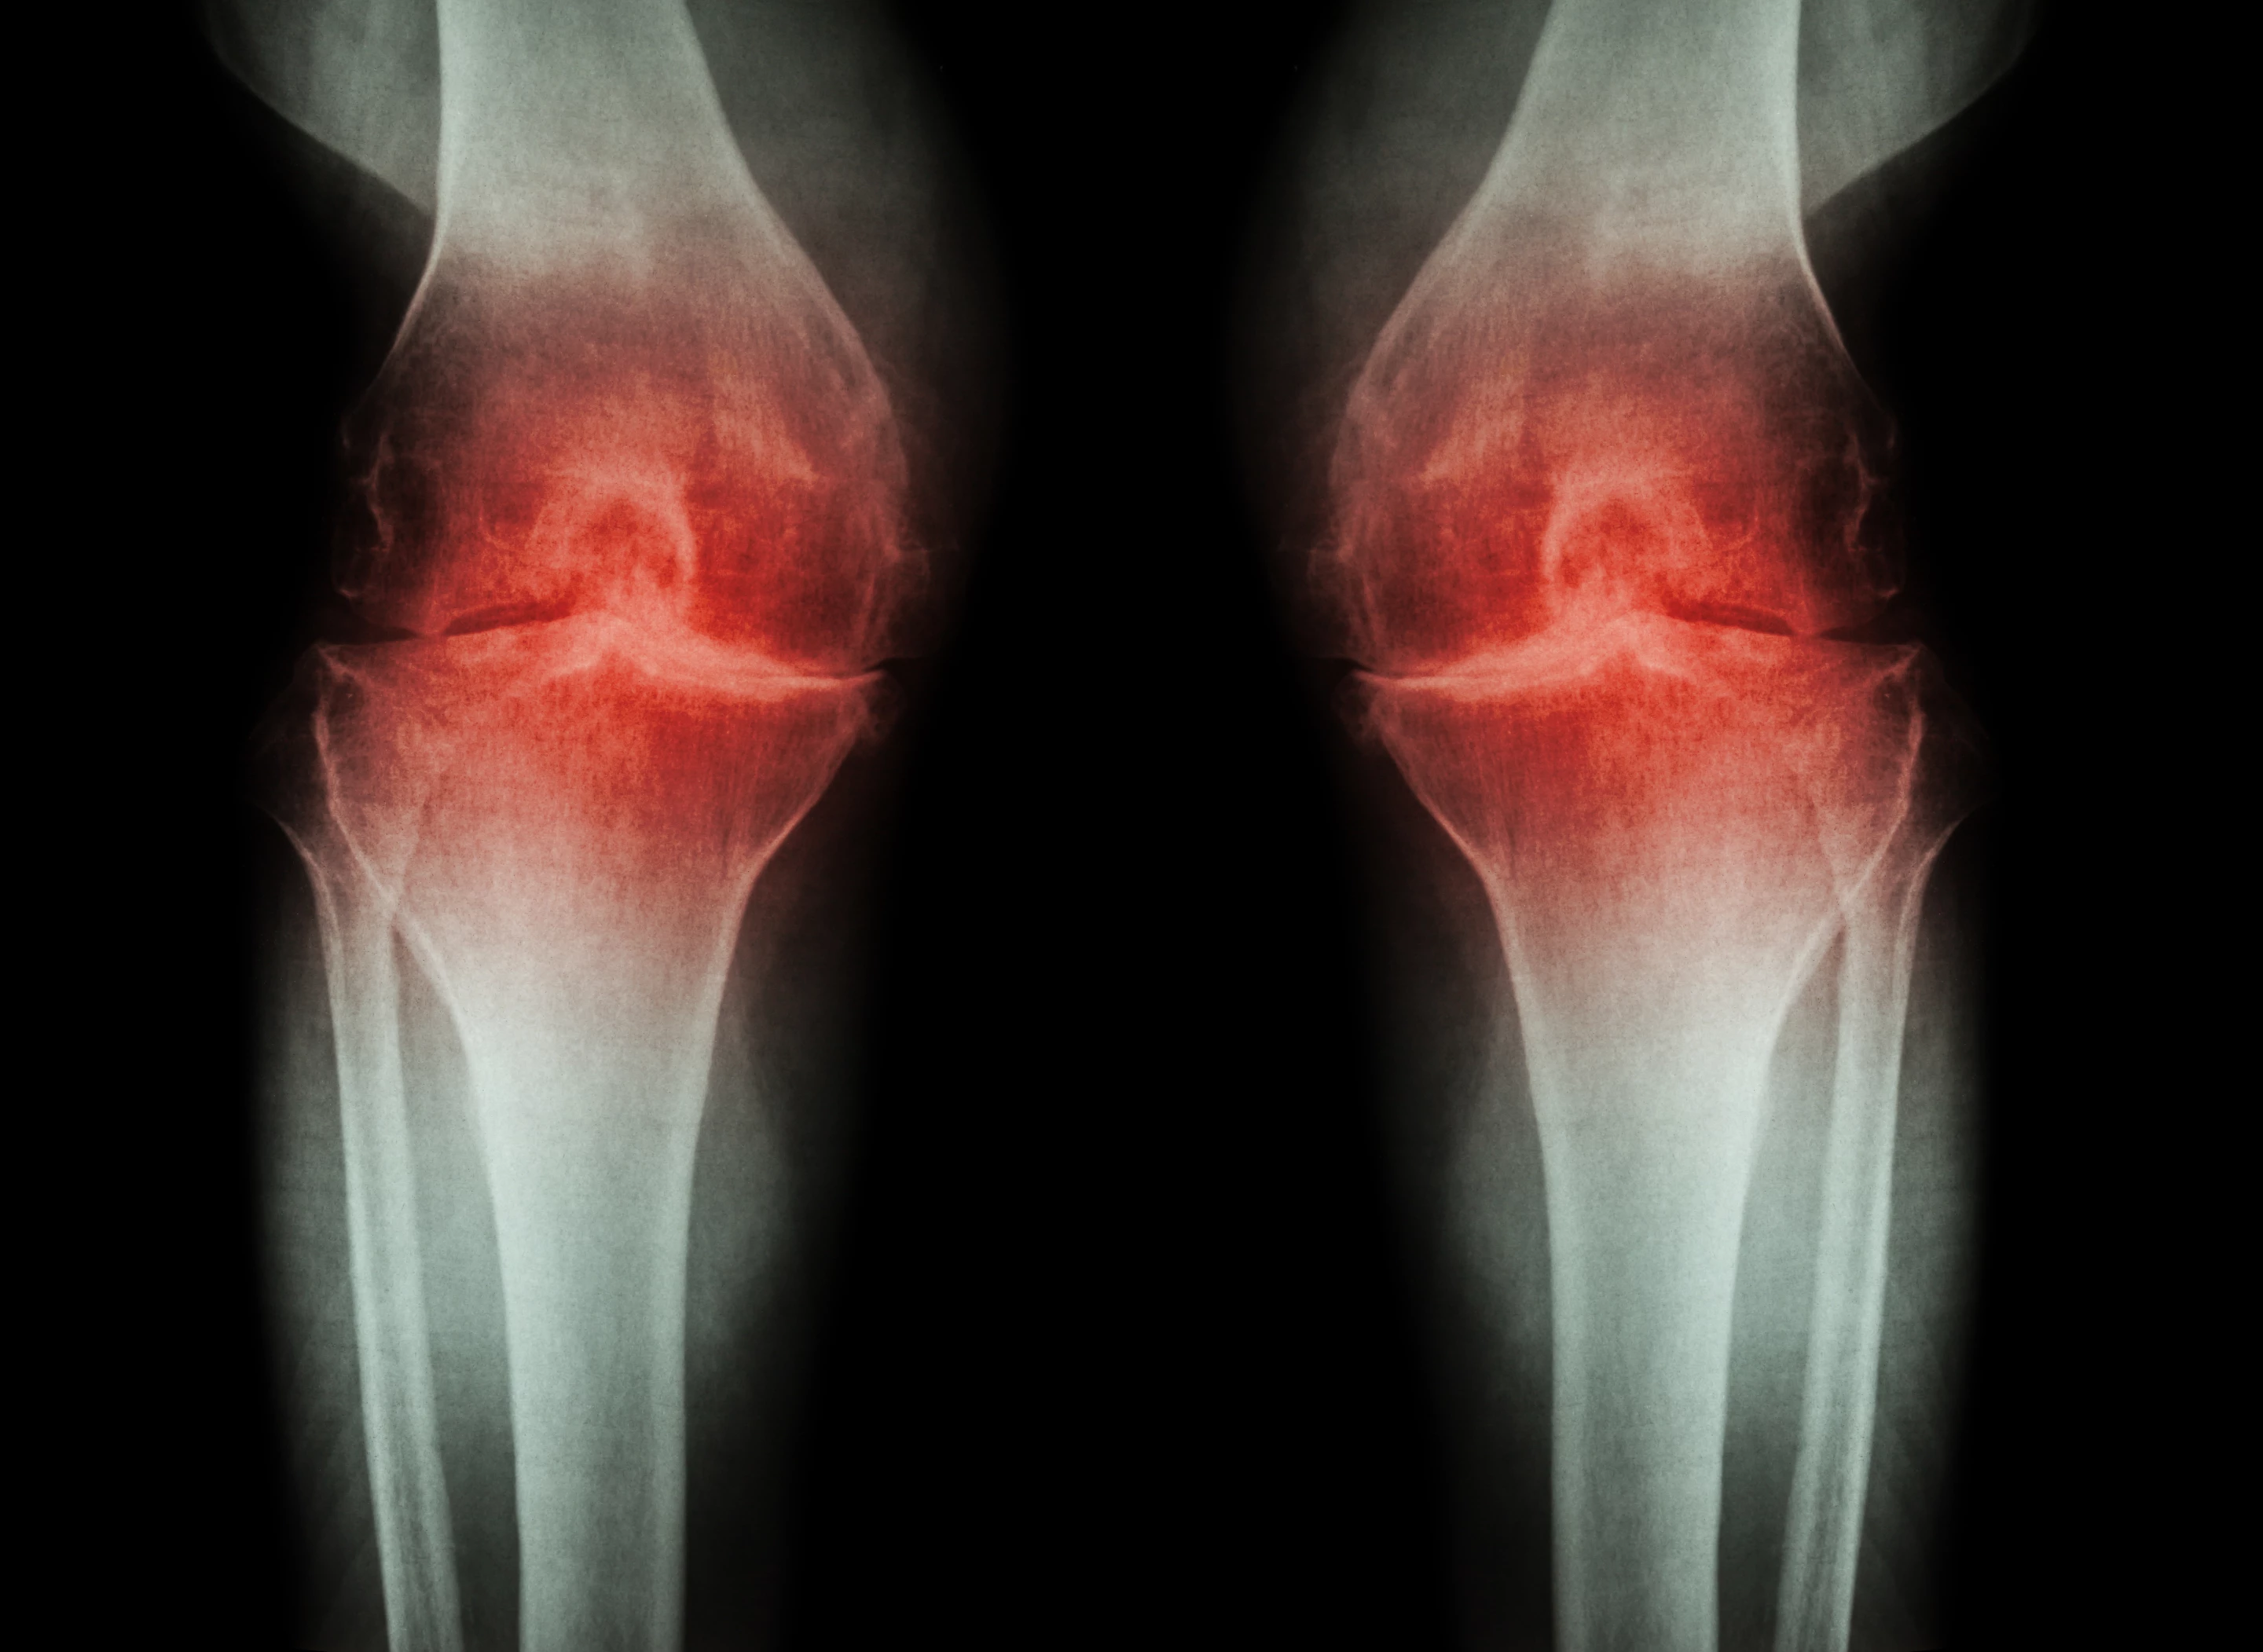

Popular anti-inflammatories linked to worse osteoarthritis progression

New data presented at the Radiological Society of North America's annual meeting suggests long-term use of non-steroidal anti-inflammatory drugs (NSAIDS), such as naproxen or ibuprofen, can be associated with hastened progression of osteoarthritis symptoms. The researchers are cautious to stress the link is still observational and more work needs to be done to understand how these drugs could be linked to worsening arthritis inflammation.

The new research, led by Johanna Luitjens from the University of California, San Francisco, focused on the association between long-term NSAID use and an arthritis symptom called synovitis. The synovial membrane is the connective tissue that lines joints like our knees or wrists, and synovitis is when that membrane becomes irritated and inflamed.

The researchers recruited over 1,000 subjects with moderate to severe osteoarthritis of the knee. Around one-quarter of the cohort received sustained NSAID therapy for over a year, while the remaining participants were not treated with the common painkillers. Each participant completed a knee MRI at the beginning of the study, and again four years later.

Evaluating a variety of MRI biomarkers of synovitis the researchers saw no long-term benefits from NSAID use over the four-year study period. In fact, markers of joint inflammation were unexpectedly worse in the NSAID group at the end of the study, compared to those not taking the anti-inflammatory drugs.

“In this large group of participants, we were able to show that there were no protective mechanisms from NSAIDs in reducing inflammation or slowing down progression of osteoarthritis of the knee joint,” said Luitjens. “The use of NSAIDs for their anti-inflammatory function has been frequently propagated in patients with osteoarthritis in recent years and should be revisited, since a positive impact on joint inflammation could not be demonstrated.”